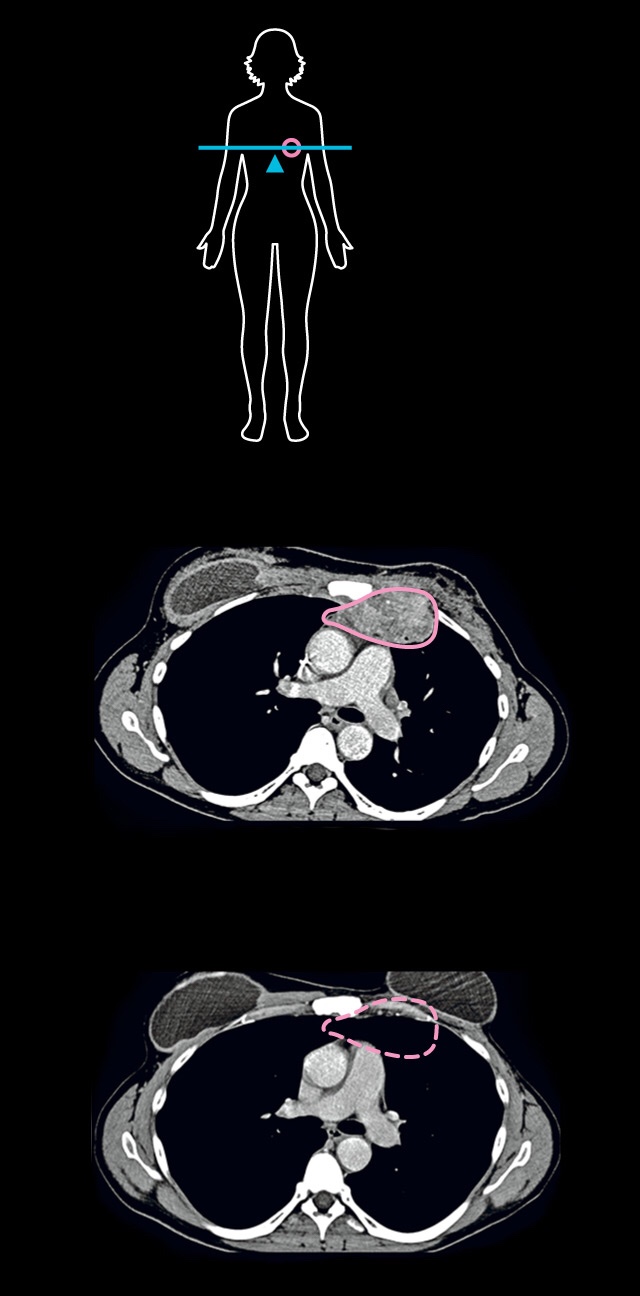

CANCER KILLERS

Judy Perkins is surrounded by white blood cells known as tumor-infiltrating lymphocytes, or TILs, which cured her breast cancer (see CT scans below). When Perkins was first diagnosed, she had her left breast removed, but the cancer returned. Despite chemotherapy, hormonal treatments, and targeted therapies, a new tumor grew in her chest. When the cancer spread, she was given months to live. But in an experimental treatment devised by Steven Rosenberg at the National Cancer Institute, Perkins was infused with 82 billion of her own TILs, which she calls her “army.”

BEFORE TREATMENT

Tumor

28 MONTHS AFTER

CT SCANS: STEVEN ROSENBERG, NATIONAL CANCER INSTITUTE